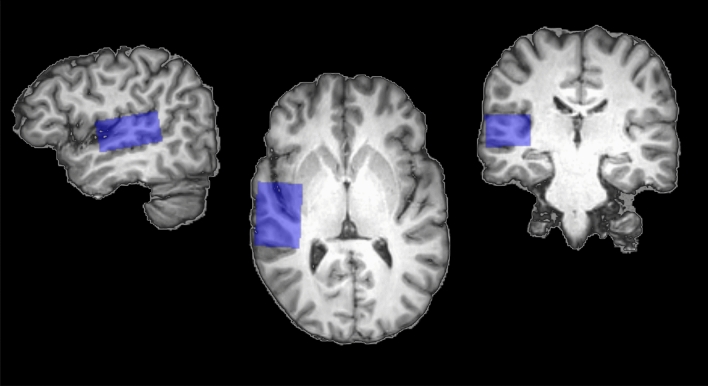

A 2D-JPRESS sequence was used for the MRS acquisition25. A nominal voxel size of 38 mm (L-R) 26 mm (I-S) 46 mm (A-P) (45.5 cm3) was analyzed using 2D-JPRESS with a minimal echo time (TE) of 30 ms48. TE was increased in steps of 2 ms with 100 steps in total. TE sampling for each step started TE/2 earlier with respect to the echo-top25. We chose a repetition time (TR) of 1600 ms and eight averages were acquired for each TE step. Water suppression was achieved via the VAPOR method49. For each TE a non-water suppressed spectrum was acquired which was used for eddy current correction and as water reference signal for metabolite quantification. The total scan time accumulated to 24 min per segment (i.e., voxel) and the right segment was always scanned first in all participants. To reduce chemical shift displacement effects and render the data collection consistent for all metabolites in the range from 1.3 to 4.0 ppm, selective saturation pulses were used (OVERPRESS)50. With this the effective voxel size reduced to 28.4 mm (L-R) 19.4 mm (I-S) 46 mm (A-P) (39.3 cm3). Figure 1 illustrates the effective voxel position and extent in an example individual T1-weighted brain MRI. The spectral bandwidth was 2000 Hz with a number of 1024 points per spectrum. Additionally we used an automated B0 shimming routine. To be able to correct for the relaxation attenuation of the water signal obtained within 2D-JPRESS, we acquired an additional non-water suppressed 1D spectrum with a long repetition time of 10 s and a series of 6 echo times (30, 63, 104, 162, 259, 600 ms) at each voxel position. No post-processing of the data was performed other than implemented by the vendor and .sdat/.spar files were used for further analysis. To quantify the final metabolites PRiOr knowledge FITting (ProFit, version 2.0) was used and adapted for water referencing23. The 2D spectrum of the water signal was fitted based on a simulated 2D water signal and using the same general model as for the metabolites (23, Equation 1) but without the model-free envelope. 1D water scans were fitted with LCModel and analyzed using in-house MATLAB code to derive correction factors for the relaxation attenuation of the 2D water signal. Segmentation was used to correct for the cerebrospinal fluid fraction in the measured voxels. With that we derived concentrations estimates in institutional units (IU) which are only roughly comparable to molal units (moles of metabolites per mass of brain water (excluding cerebrospinal fluid)), as we have not corrected for T1 or T2 relaxation attenuation of the metabolite signal. Cramer-Rao Lower Bounds percentage values resulting from ProFit fitting were used to assess spectral quality23.

Figure 1.

MRS ROI voxel. Right voxel (radiological convention) colored in blue and in sagittal, horizontal, and coronal view (from left to right). The voxel covers Heschl’s Gyrus, parts of superior temporal gyrus, and insular cortex. No differences in voxel size or composition between the two hemispheres were found.